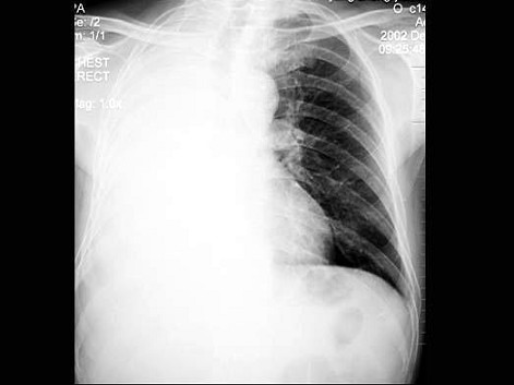

32、单项选择题

男,65岁,胸痛,胸片检查如图,下列诊断中最可能的是()

A.右肺胸膜肥厚

B.右肺不张

C.右侧胸腔积液

D.右肺炎症

E.以上都不对